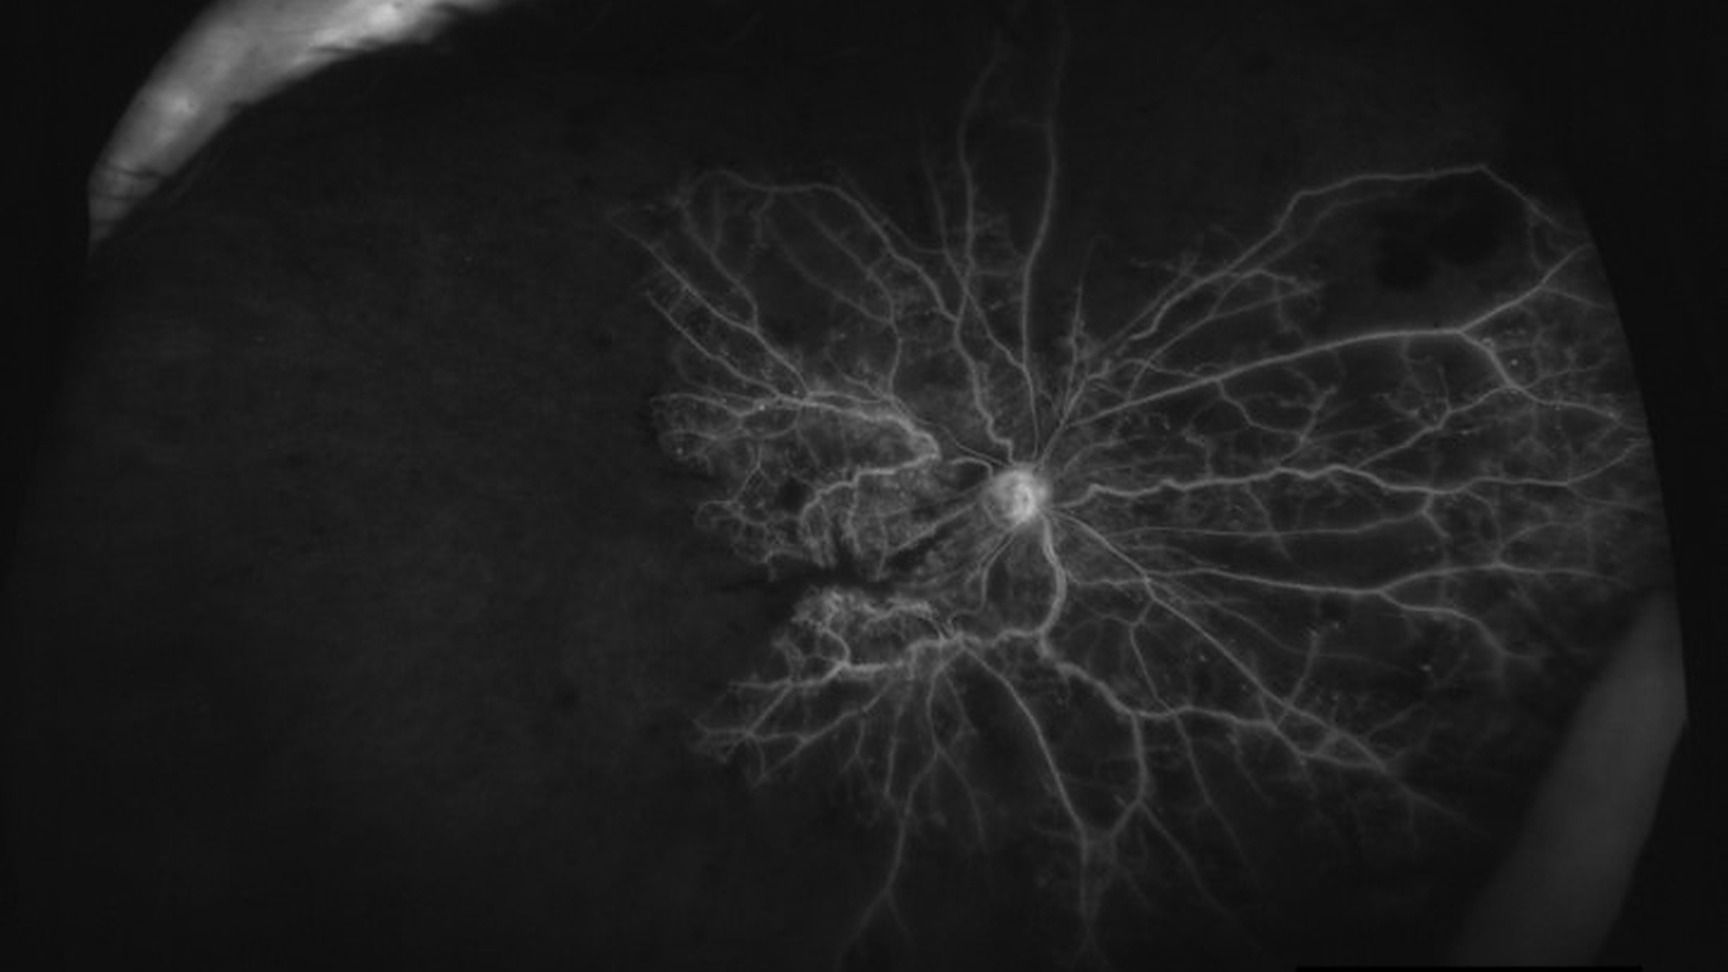

Quels examens pour le diagnostic et le suivi des occlusions veineuses rétiniennes ?

Les occlusions de veine ou de branche rétinienne (OVR et OBVR) sont des pathologies rencontrées en consultation ophtalmologique, d'autant plus avec le vieillissement de la population.

Il est essentiel de savoir identifier leurs signes cliniques en imagerie multimodale et surtout savoir prescrire et réaliser les bons examens complémentaires à leurs diagnostics et leurs prises en charge.

Identifier les signes cliniques des OVR et l'apport de chaque examen complémentaire dans le diagnostic et le suivi

Surveiller la macula mais ne pas négliger la recherche d'une ischémie périphérique pour limiter les risques de glaucome néovasculaire